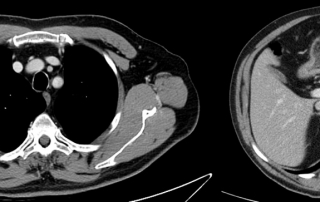

Scanner thorax abdomen pelvien : masse médiastinale antérieure et supérieure, absence d’atteinte du pédicule vasculaire, absence de nodule pulmonaire, scanner sous-diaphragmatique normal. Cible médiastinale taille 94 x 67 mm

TEP-FDG masse médiastinale hypermétabolique isolée